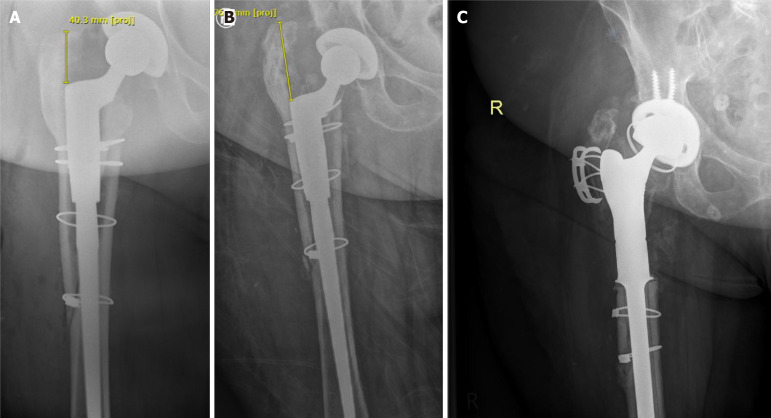

Abstract Image